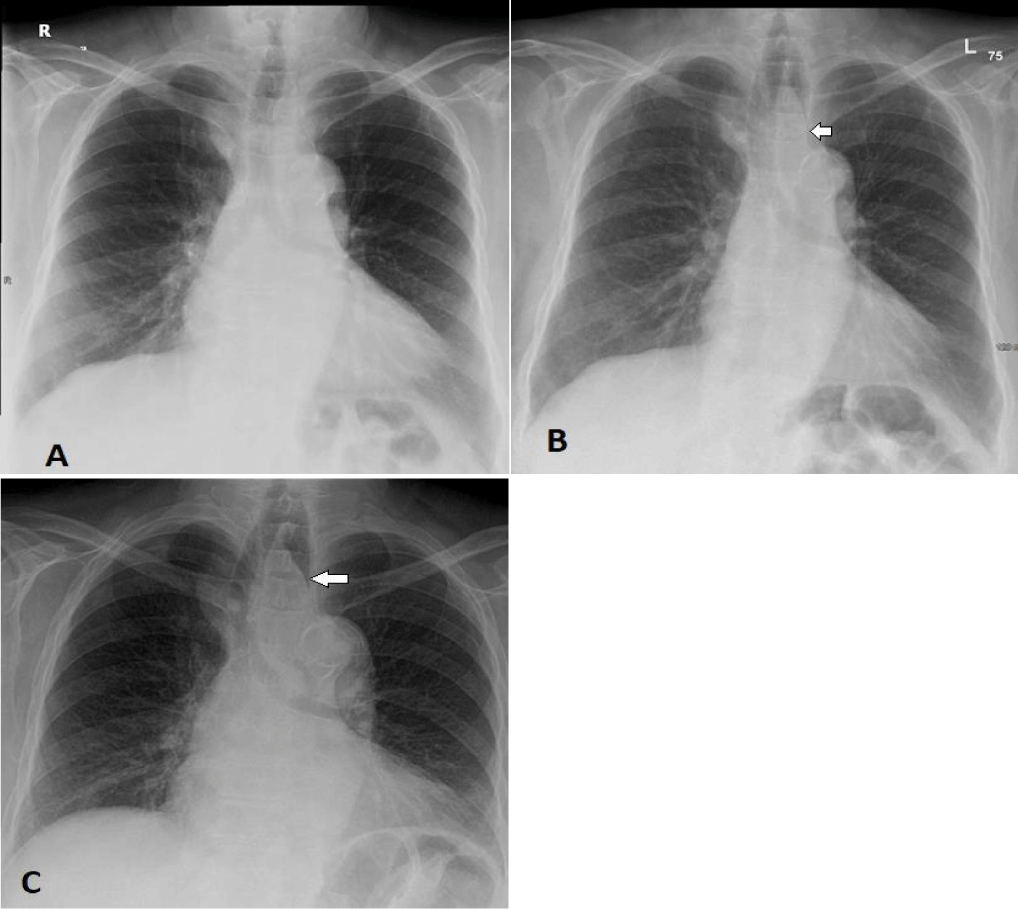

A chest X-ray (Figure1) revealed a soft tissue density in the middle mediastinal compartment, causing compression of the oesophageal column with smooth tapering. A further assessment by CT scan of the chest (Figure 2) identified a pedunculated, fat-density mass in the upper third of the oesophagus, resulting in obstruction and mild dilation of the proximal oesophagus, consistent with the lesion observed in the previous radiograph. No oesophageal thickening or abnormal enhancement was present, no soft tissue component and there was no enlargement of local lymph nodes.